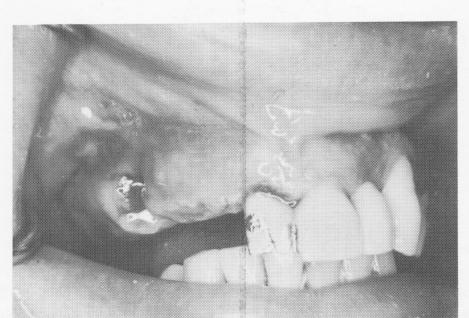

Fig. 7-90. To remove a failing implant in a posterior situation, the buccogingival third of the crown may be removed to get at the implant.

1 Buccogingival third of crown removed to remove failed posterior implant